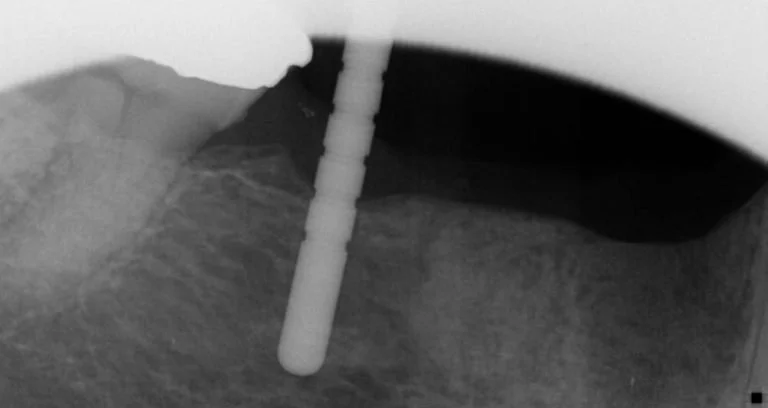

Diagnostic pre-treatment image 1

Due to the extent of the infection, tooth 44 was extracted, the site carefully curetted, and then left to heal for three months prior to bone volume assessment with a cone beam tomograph (Soridex).

Once healing and adequate bone volume above the mandibular canal had been confirmed, two Bioconcept 3.3mm x 10mm tissue level implants were placed in sites 44 and 46. Several careful progressive intraoperative periapical radiographs were taken to confirm vertical position relative to the mandibular canal. Both implants were then placed with a primary stability of over 30 Ncm as a one stage surgical procedure, and 2mm healing abutments were then secured.